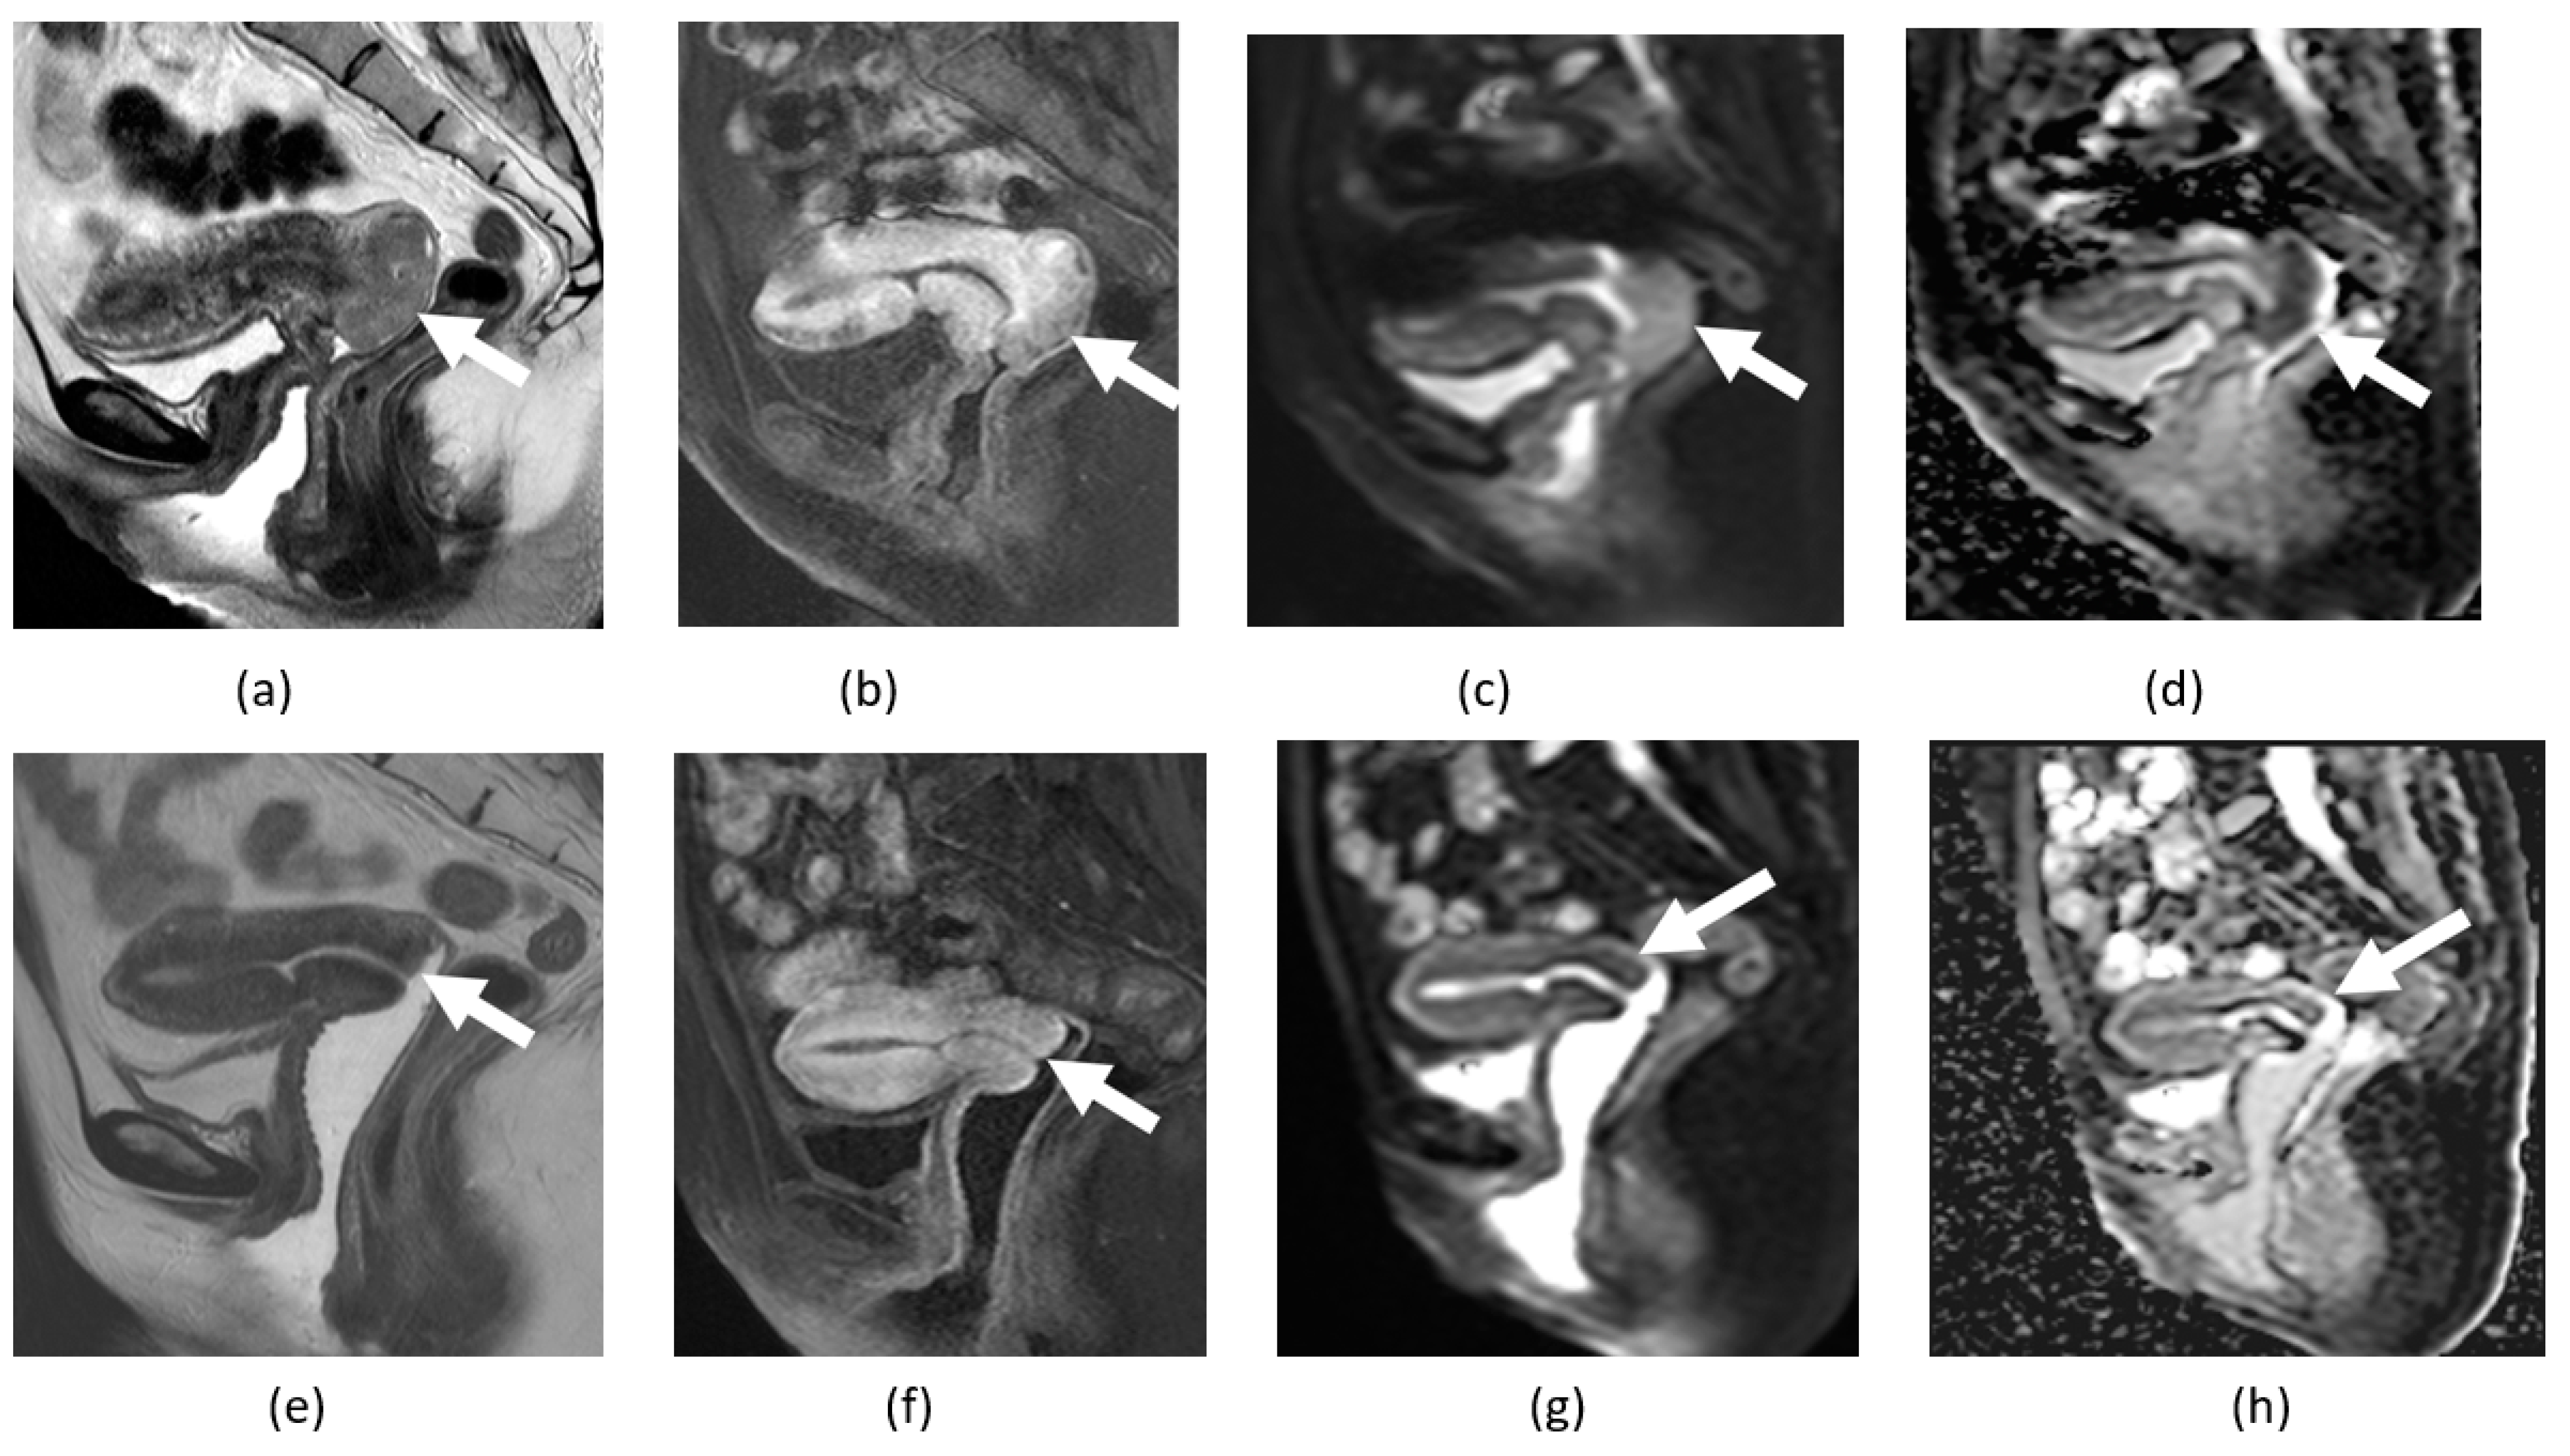

3.3. Endometriosis